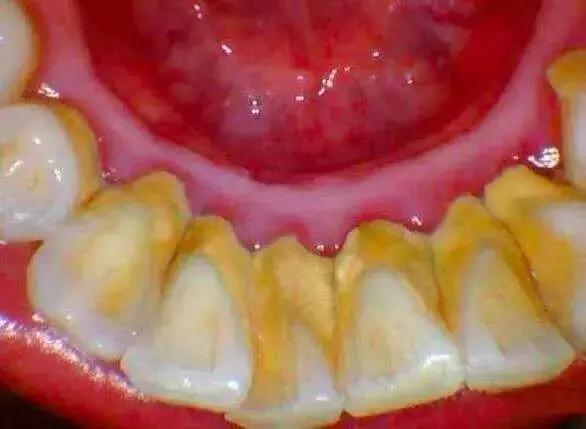

牙结石

当牙结石达到一定程度,就会刺激牙龈发炎,刷牙出血。

洗牙前后对比